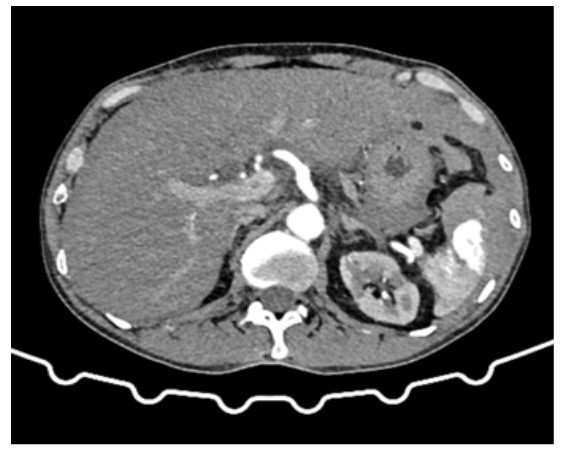

55-year-old male patient shop keeper by occupation, presented to ED with complaints of left shoulder pain for 1 day. He was initially treated in a local hospital near his home for the same complaints. But there was no symptomatic improvement in pain hence he was referred to our hospital. He did not disclose any chest pain, diaphoresis, difficulty in breathing, fever, or pain abdomen. On examination his cardiorespiratory parameters were within normal limits (Non-invasive blood pressure of 118/78 mmhg, pulse rate of 82 beats per minute, respiratory rate of 16 per minute, peripheral oxygen saturation of 98% on room air). On local examination there was no visible contusions or tenderness over the left shoulder, range of motion was full but painful. The abdominal examination showed minimal tenderness in the left hypochondrium with normal bowel sounds. Other systemic examination was unremarkable. He reported an initial Pain score of 6/10 at the left shoulder joint by numerical rating scale and iv analgesics was given. Further history revealed that the patient had an accidental slip and fall onto a hard surface while working in his shop with impact on his abdomen 4 days back. Extended Focused Assessment with Sonography for Trauma (E-FAST) scan showed fluid collection in the suprapubic view (Figure 1). Electrocardiogram was normal. In view of positive E-FAST, a contrast enhanced computed tomography scan of abdomen was performed and confirmed that the patient had a Grade V splenic injury with moderate hemoperitoneum (Figure 2). He was then taken to operating room for emergency splenectomy.

Figures 2: Active contrast extravasation along the anterior splenic parenchyma, large sub capsular hematoma covering >50% of the surface area-AAST grade V splenic injury.